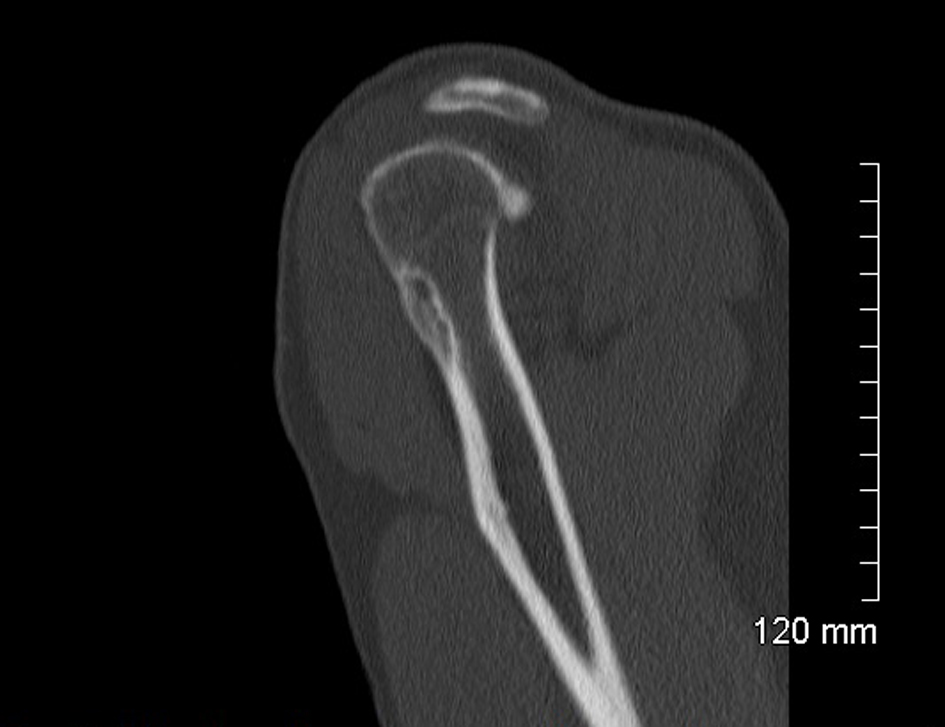

A 52-year-old male consulted for sudden swelling in the left deltoid region without his being aware of any recent traumatism. The clinical examination confirmed the painless swelling, which did not cause functional disability, suggesting a rotator cuff tear. An ultrasound did not show anything in particular. An X-ray found a hypodense lesion in the cortical bone on the upper third of the humerus (Fig. 1). The MRI confirmed a penetrating tear in the supraspinatus muscle and a lesion of the infraspinatus muscle. A “small geode” was found under the cartilage of the humeral head outside the bicipital groove (Fig. 2). The CT scan revealed a 30 mm hypodense lacunar formation on the front cortical bone of the upper humerus metaphysis, surrounded by thickened cortical bone resembling an osteoid osteoma (Fig. 3).

![]() Click for large image | Figure 3. CT hypodense lacunar formation on the front cortical bone. |